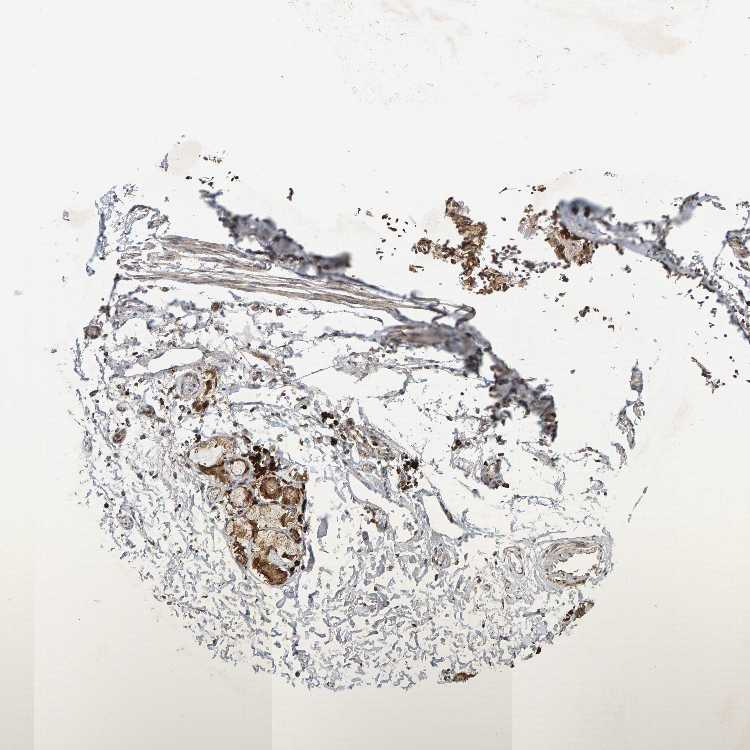

SOFT TISSUE 1 - Antibody stainingi

Antibody staining in the annotated cell types in the current human tissue is reported as not detected, low, medium, or high, based on conventional immunohistochemistry profiling in selected tissues. This score is based on the combination of the staining intensity and fraction of stained cells.

Each image is clickable and will lead to virtual microscopy that enables deeper exploration of all samples and also displays staining intensity scores, fraction scores and subcellular localization as well as patient and tissue information for each sample.

Antibody HPA023310Antibody HPA027421

Chondrocytes -Medium

Fibroblasts MediumMedium

Peripheral nerve LowMedium